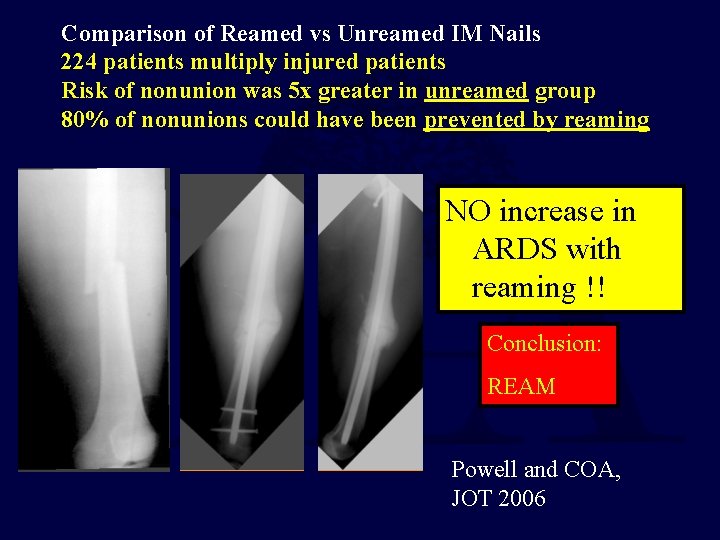

Comparison of Reamed vs Unreamed IM Nails 224 patients multiply injured patients Risk of nonunion was 5 x greater in unreamed group 80% of nonunions could have been prevented by reaming NO increase in ARDS with reaming !! Conclusion: REAM Powell and COA, JOT 2006